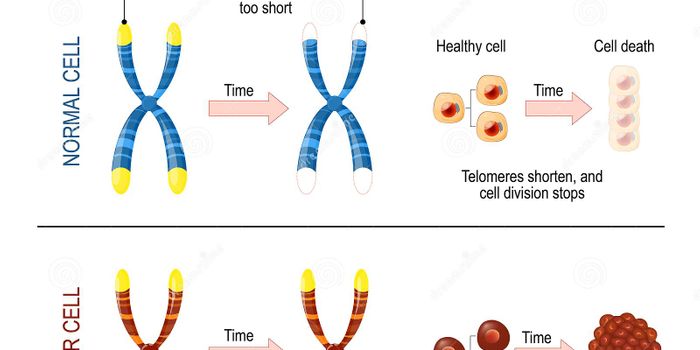

SEP 15, 2019ImmunologyNew research shows a transcriptase that helps time cell death varies in expression, and is unusually localized, in cance ...